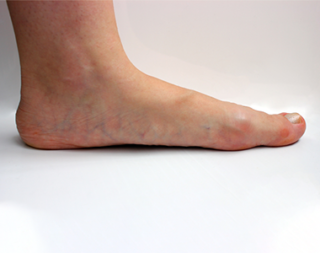

Deep Vein Thrombosis occurs when a clot develops in deep veins, typically in the leg. Swelling or pain may result, although there are no signs in some cases. Certain health conditions affect clotting and raise DVT risk. Prolonged periods of immobilisation, such as bed rest or travel, can also induce clotting. Clots may separate, travel through the veins, and block blood circulation. This condition, called pulmonary embolism (PE), is dangerous. When both DVT and PE occur, they are called venous thromboembolism.

DVT, or Deep Vein Thrombosis, is the formation of blood clots within the deep veins of the legs. Once these clots become dislodged and migrate to the lungs, they may cause a blockage in the arteries, known as a pulmonary embolism. These conditions are called venous thromboembolism and can occur due to genetic and acquired risk factors.

Pulmonary embolism or deep vein thrombosis is a serious medical condition. Blood clot formation is its primary cause. When this clot enters the bloodstream, there’s a high risk for it to reach the lungs. Consequently, the clot hinders the lung arteries and curtails the oxygen and blood flow. Usually, it develops inside the deeper veins in the legs. When detected, the pulmonary embolism treatment must be immediate as it may prove to be fatal without immediate care.

Varicose veins are the twisted, swollen and bulging veins that appear in blue, red and skin color, just beneath the surface of the skin. They occur mostly in the legs and feet, causing aching pain and discomfort in the legs.